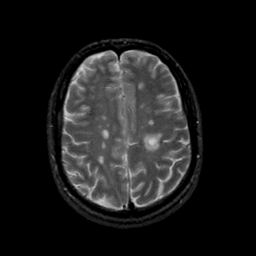

MR Study #21, November 3, 1991 -- Slice #36